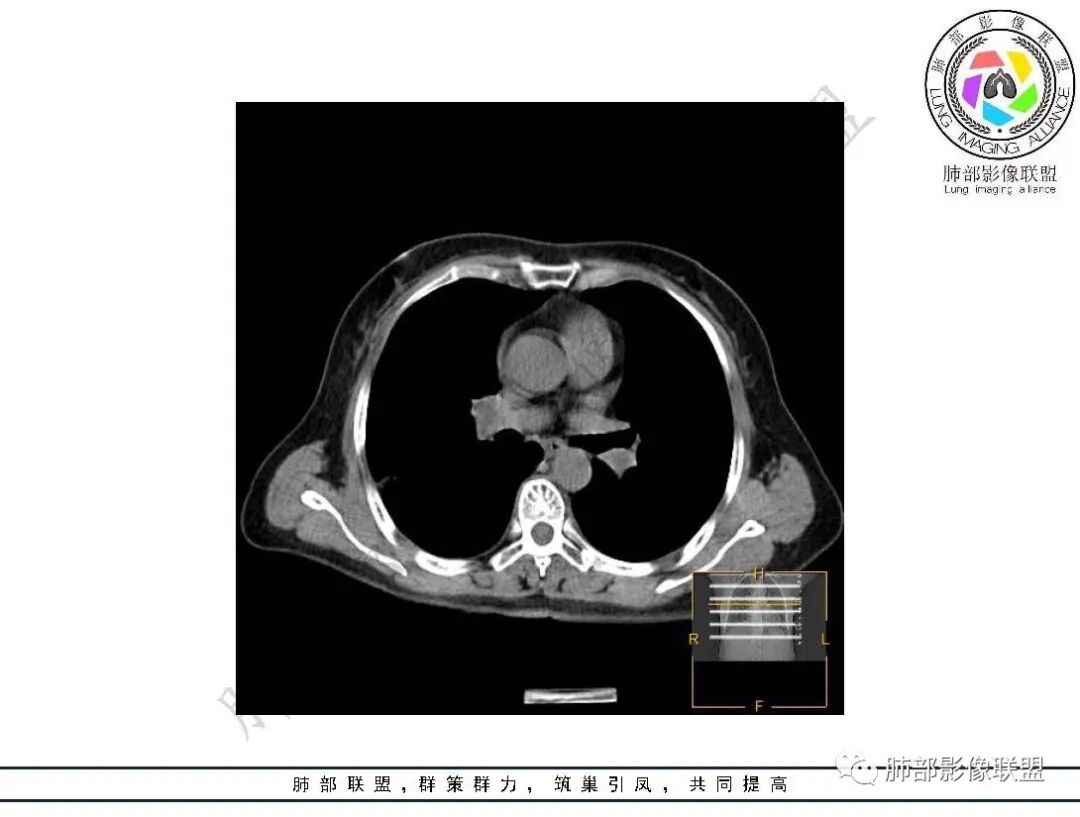

2、影像所见:右肺上叶后段混合密度磨玻璃影mGGN,整体膨隆为主,局部收缩,局部边缘可疑月牙铲。周围磨玻璃影边界清楚,边缘分叶,细细观察这种清楚的弧形边界,与小叶间隔是否高度契合?!

结节内血管影增粗。病灶附近血管纠集,临近胸膜轻度增厚,叶间胸膜轻度牵拉移位。综合考虑恶性,腺癌可能。(局部胸膜增厚,考虑为肿块局部牵拉为主造成的)。